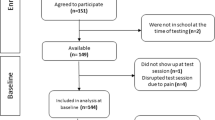

The adolescent subjects were recruited from the male youth teams of two national premier league teams: the football club NK Maribor and the ice hockey team HK Olimpija Ljubljana. The medical and sporting history of the potential candidates was first recorded and checked. Participants were required to participate in regular sport for at least 3 years prior to recruitment, i.e. 3–5 training sessions per week plus competitions according to the age group programme. Individuals with a history of severe lower limb injury or surgery of any kind, known systemic musculoskeletal disorders, malformations and deformities or joint hyperlaxia were excluded. Based on the selection criteria, 90 football and 38 ice hockey players aged 12–16 years were included in the study. They were divided into 5 age groups: from 12 (≥ 12 and < 13) to 16 (≥ 16 and < 17) years.

The distribution of athletes among age groups was similar: in the 12-year-old group there were 19 footballers and 8 ice hockey players, in the 13-year-old group there were 20 footballers and 8 ice hockey players, in the 14-year-old group there were 19 footballers and 7 ice hockey players, in the 15-year-old group there were 15 footballers and 8 ice hockey players, and in the 16-year-old group there were 17 footballers and 7 ice hockey players. There was no significant difference between the sport groups in terms of age at initiation of sport participation (football = 7.1 ± 1.2 years; ice hockey = 6.8 ± 2.1 years; p = 0.553) and in terms of duration of participation in each sport (football = 6.8 ± 1.7 years; ice hockey = 5.7 ± 2.3 years; p = 0.668).